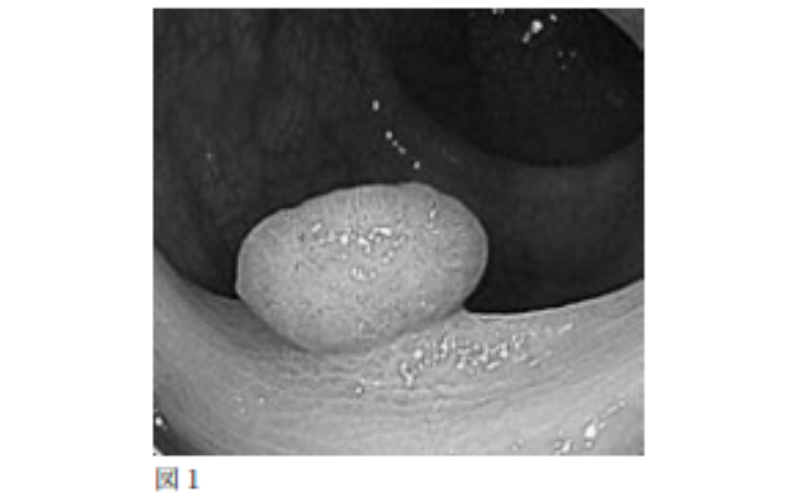

大腸ポリープ(図1)はその構造(組織)により、大腸がんになる可能性がある腫瘍性のポリープ(腺腫)とそれ以外(非腺腫)に分けられ、大腸ポリープの多くが腺腫です。